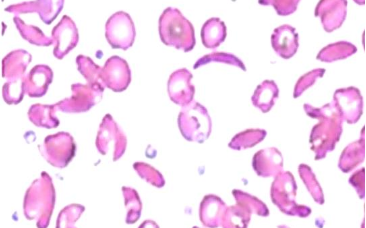

A 20 years old male comes with fever since 5 days. Fever is episodic. The peripheral blood film is shown below.

What abnormality (Micrograph name) do you see in this smear?

- Ring form - Malarial parasite inside RBCs Z

What is your diagnosis?

- Malaria

Mention 2 causes of anemia in this infection? Z

- **Mechanical destruction of RBCs

- Reduced erythropoiesis in the bone marrow